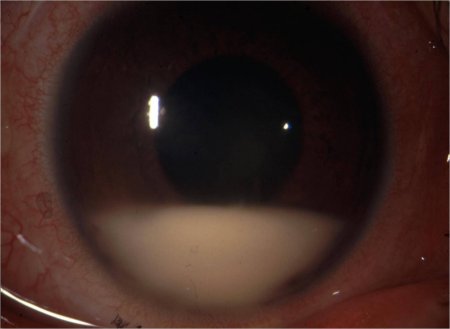

Eye involvement [Figure caption and citation for the preceding image starts]: HypopyonFrom the collection of Yusuf Yazici, MD [Citation ends].

Approximately one-half of patients have eye involvement with uveitis.[7]

More severe in men.[7]

Hypopyon, the precipitation of inflammatory cells in the anterior chamber of the eye, is seen in 20% of patients with eye involvement and is a marker for severe inflammation.[7] Hypopyon is virtually pathognomonic.[3]